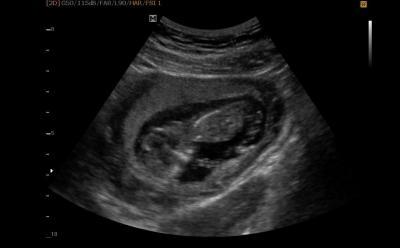

Und alles sieht gut aus! Krümel hat die richtige SSL, Herz, Magen und Blase sind da und tun ihren Dienst, Nackenfalte sieht harmlos aus. Ich bin super glücklich! Das einzig dumme ist, dass mein Krümelchen heute morgen Hummeln im Hintern hatte, und mein FA schon Schwierigkeiten, ein gutes Bild zum Messen zu bekommen. Für ein schönes Bild fehlte Krümelchen dann wirklich jeglicher Sinn. Mein Mann hat sich tierisch über das hüpfende und drehende etwas im Ultraschall amüsiert! Also, kein tolles Bild zum angeben bei der Familie, obwohl mein FA extra lange über den Bauch aus allen möglichen Blickwinkeln geschallt hat. Aber immerhin sieht man eine tolle Wirbelsäule! Allen anderen mit FA Terminen heute wünsche ich nur die besten Nachrichten und liebe Krümel mit Sinn fürs posieren!